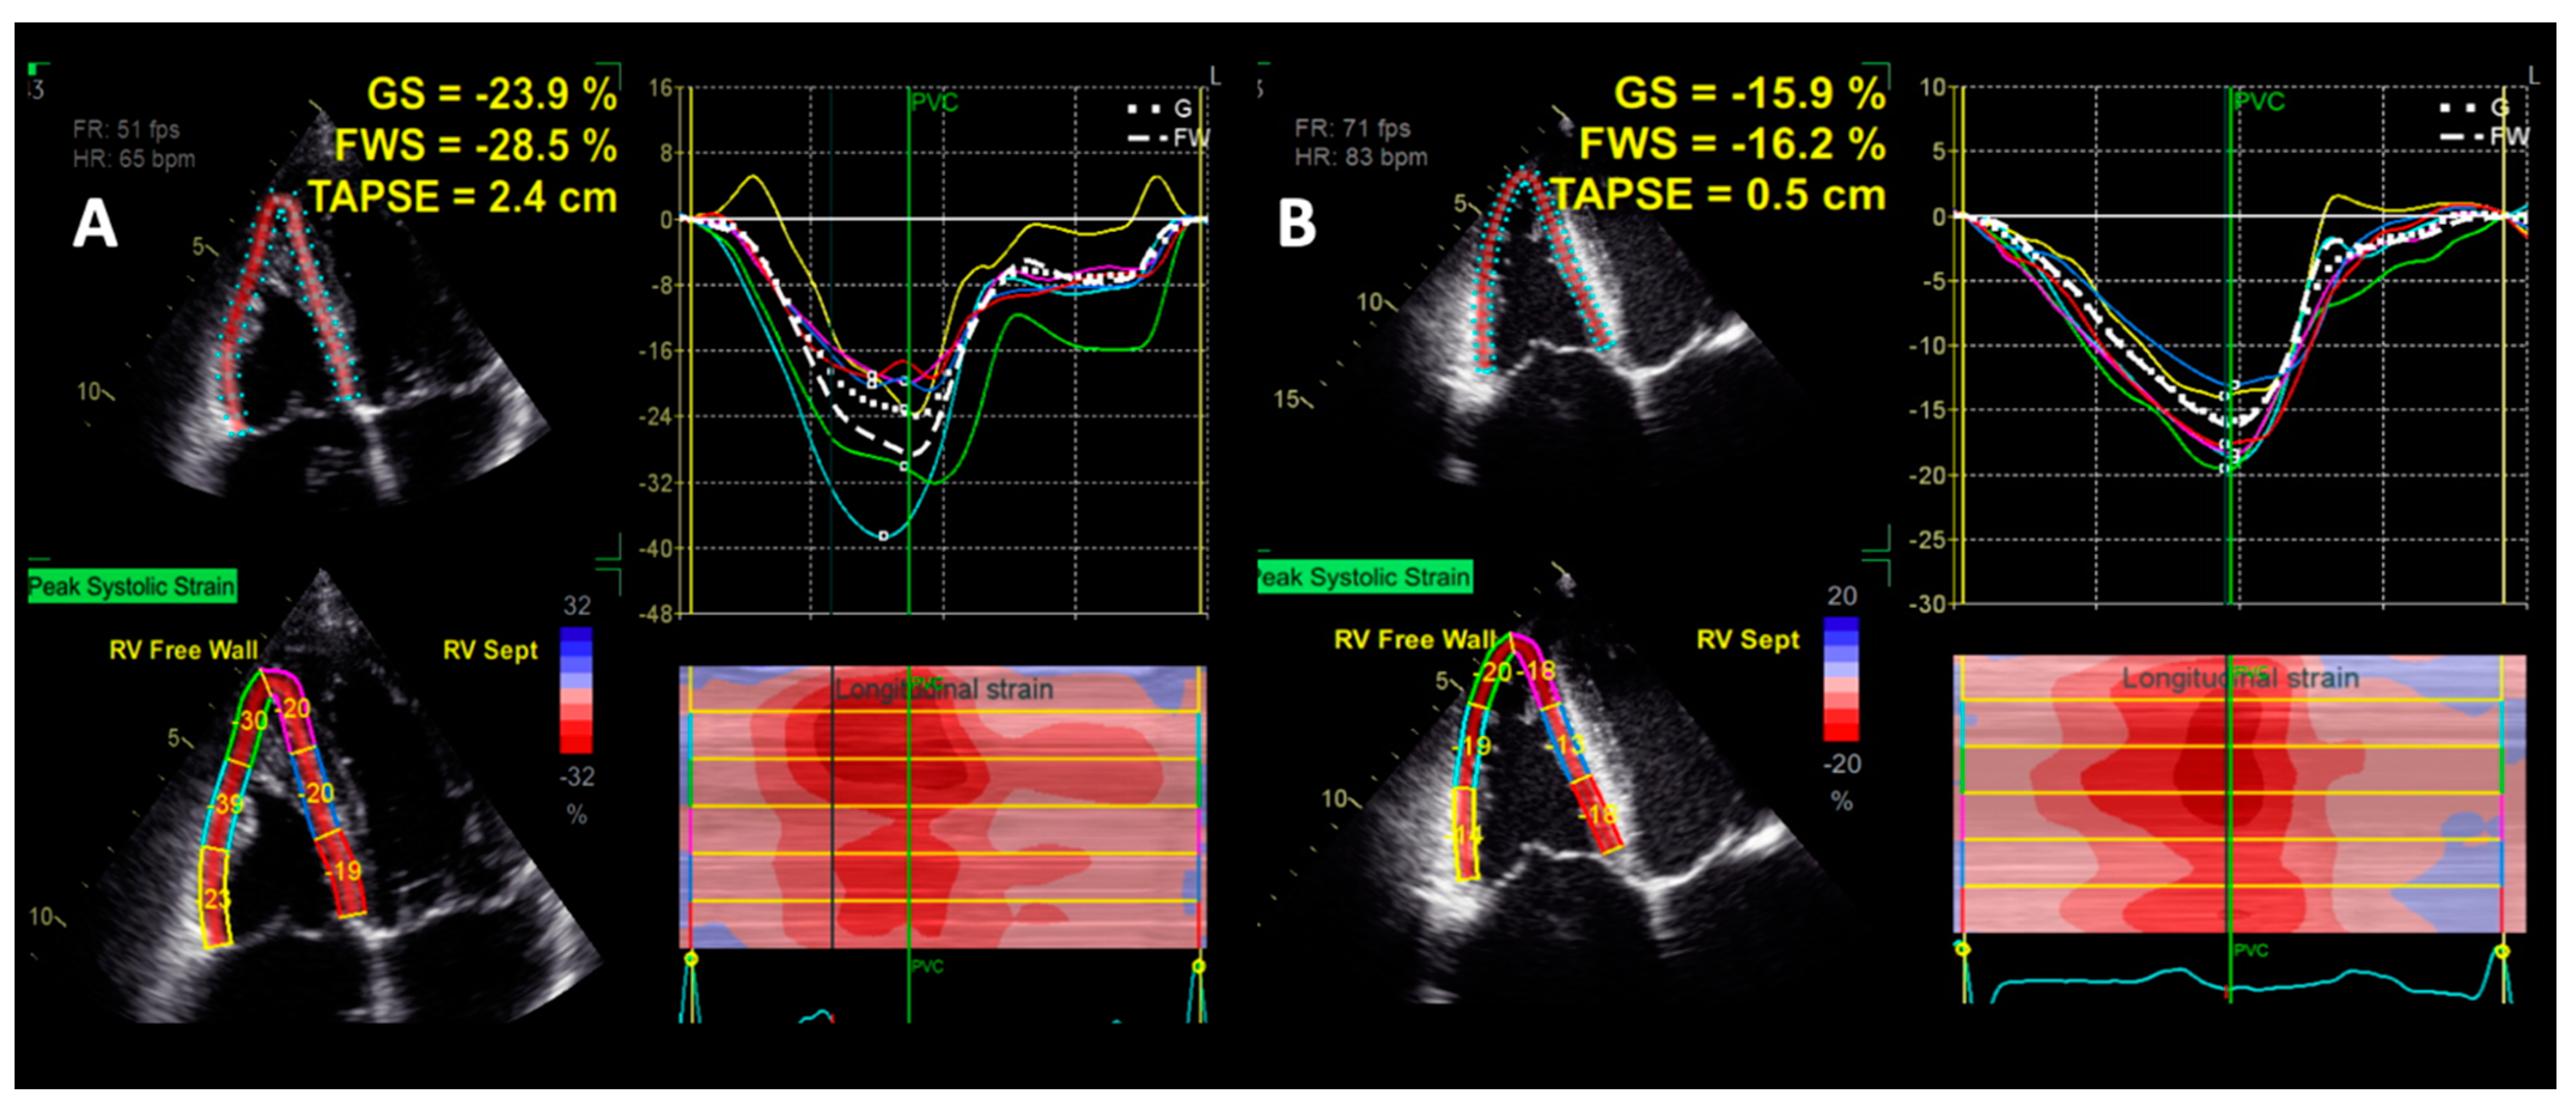

4.1.5. Right Ventricular Strain by Speckle-Tracking Echocardiography